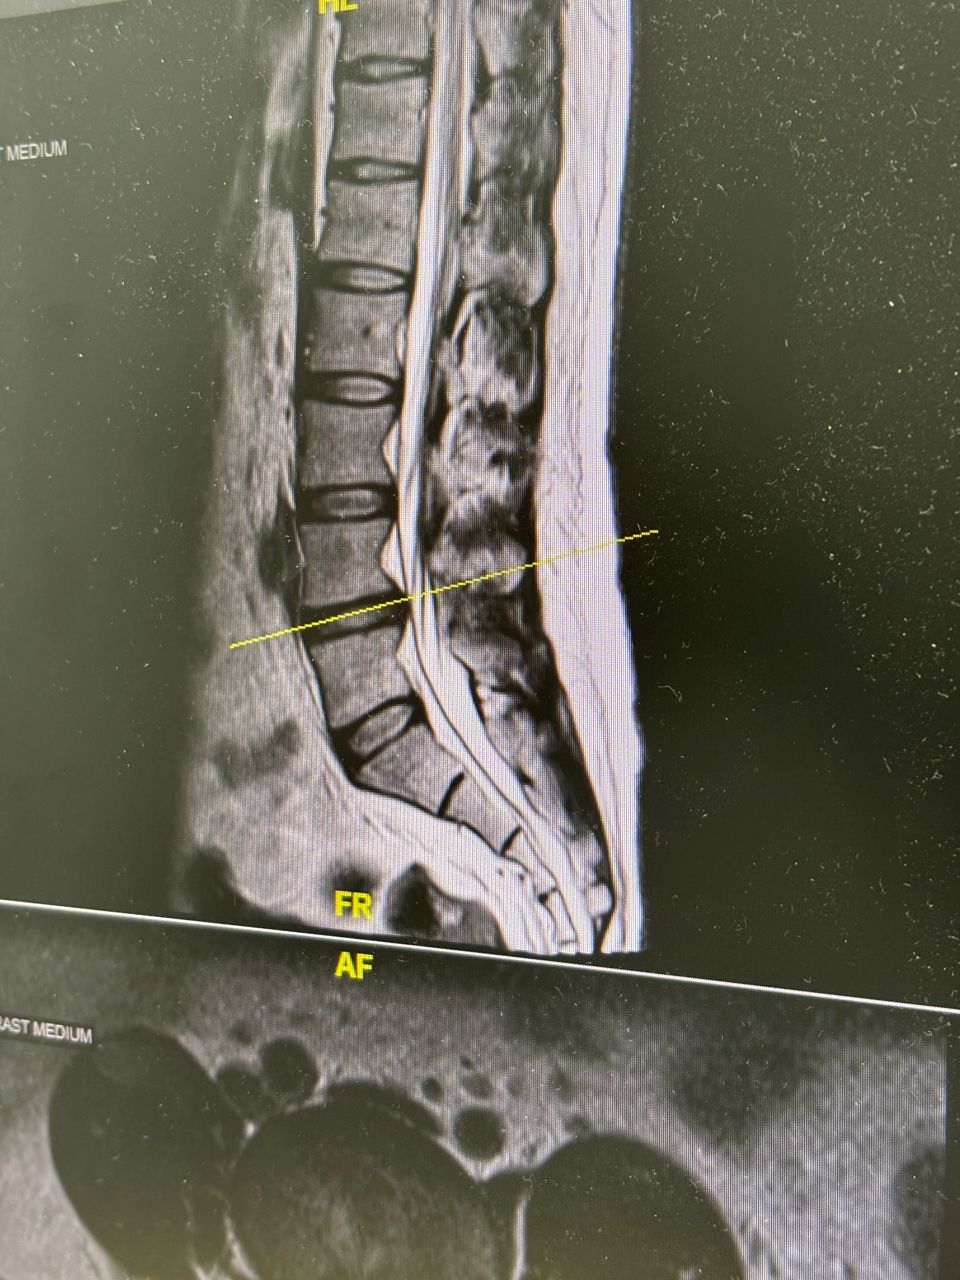

腰痛已經是10年的老毛病了 但近半年突然增加了大腿到小腿極爲酸痛的症狀 坐30分鐘就痛到不行 而且腳也慢慢開始有無力 不能久站的情形 照MRi醫生説腰椎L4-L5有突出 然後L5到S1椎間盤也退化 吃止痛藥 拉腰都沒什麼效果 醫生說可以試試看高頻熱凝療法 不知道有沒有人做過 安全性和效果如何? 謝謝 --